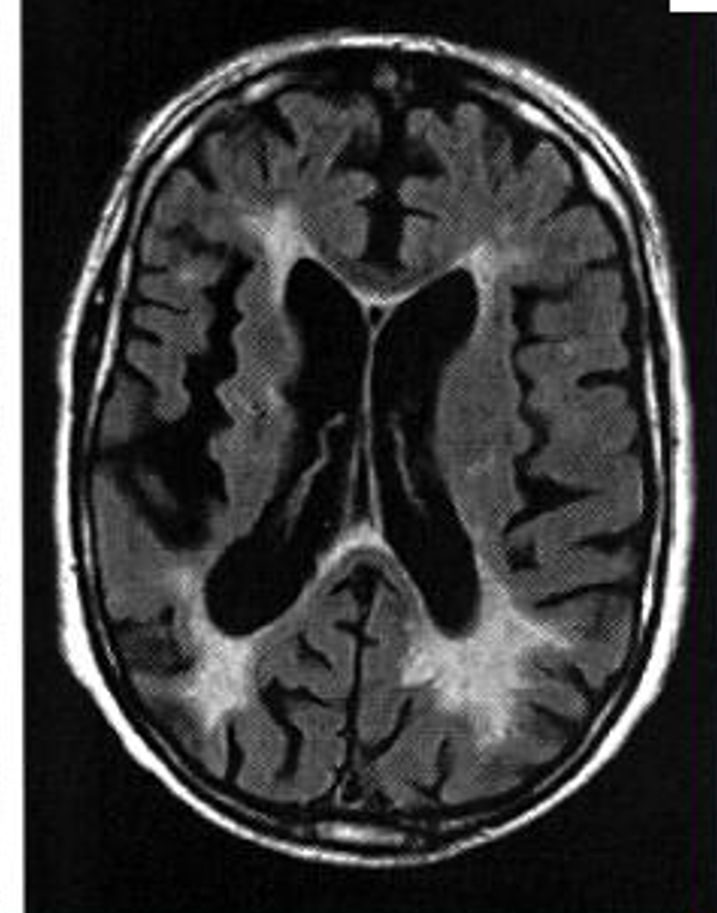

Diagnostic?

Leuco-araïose

+ lacunes =petits hypersignaux de la substance blanche et du cortex